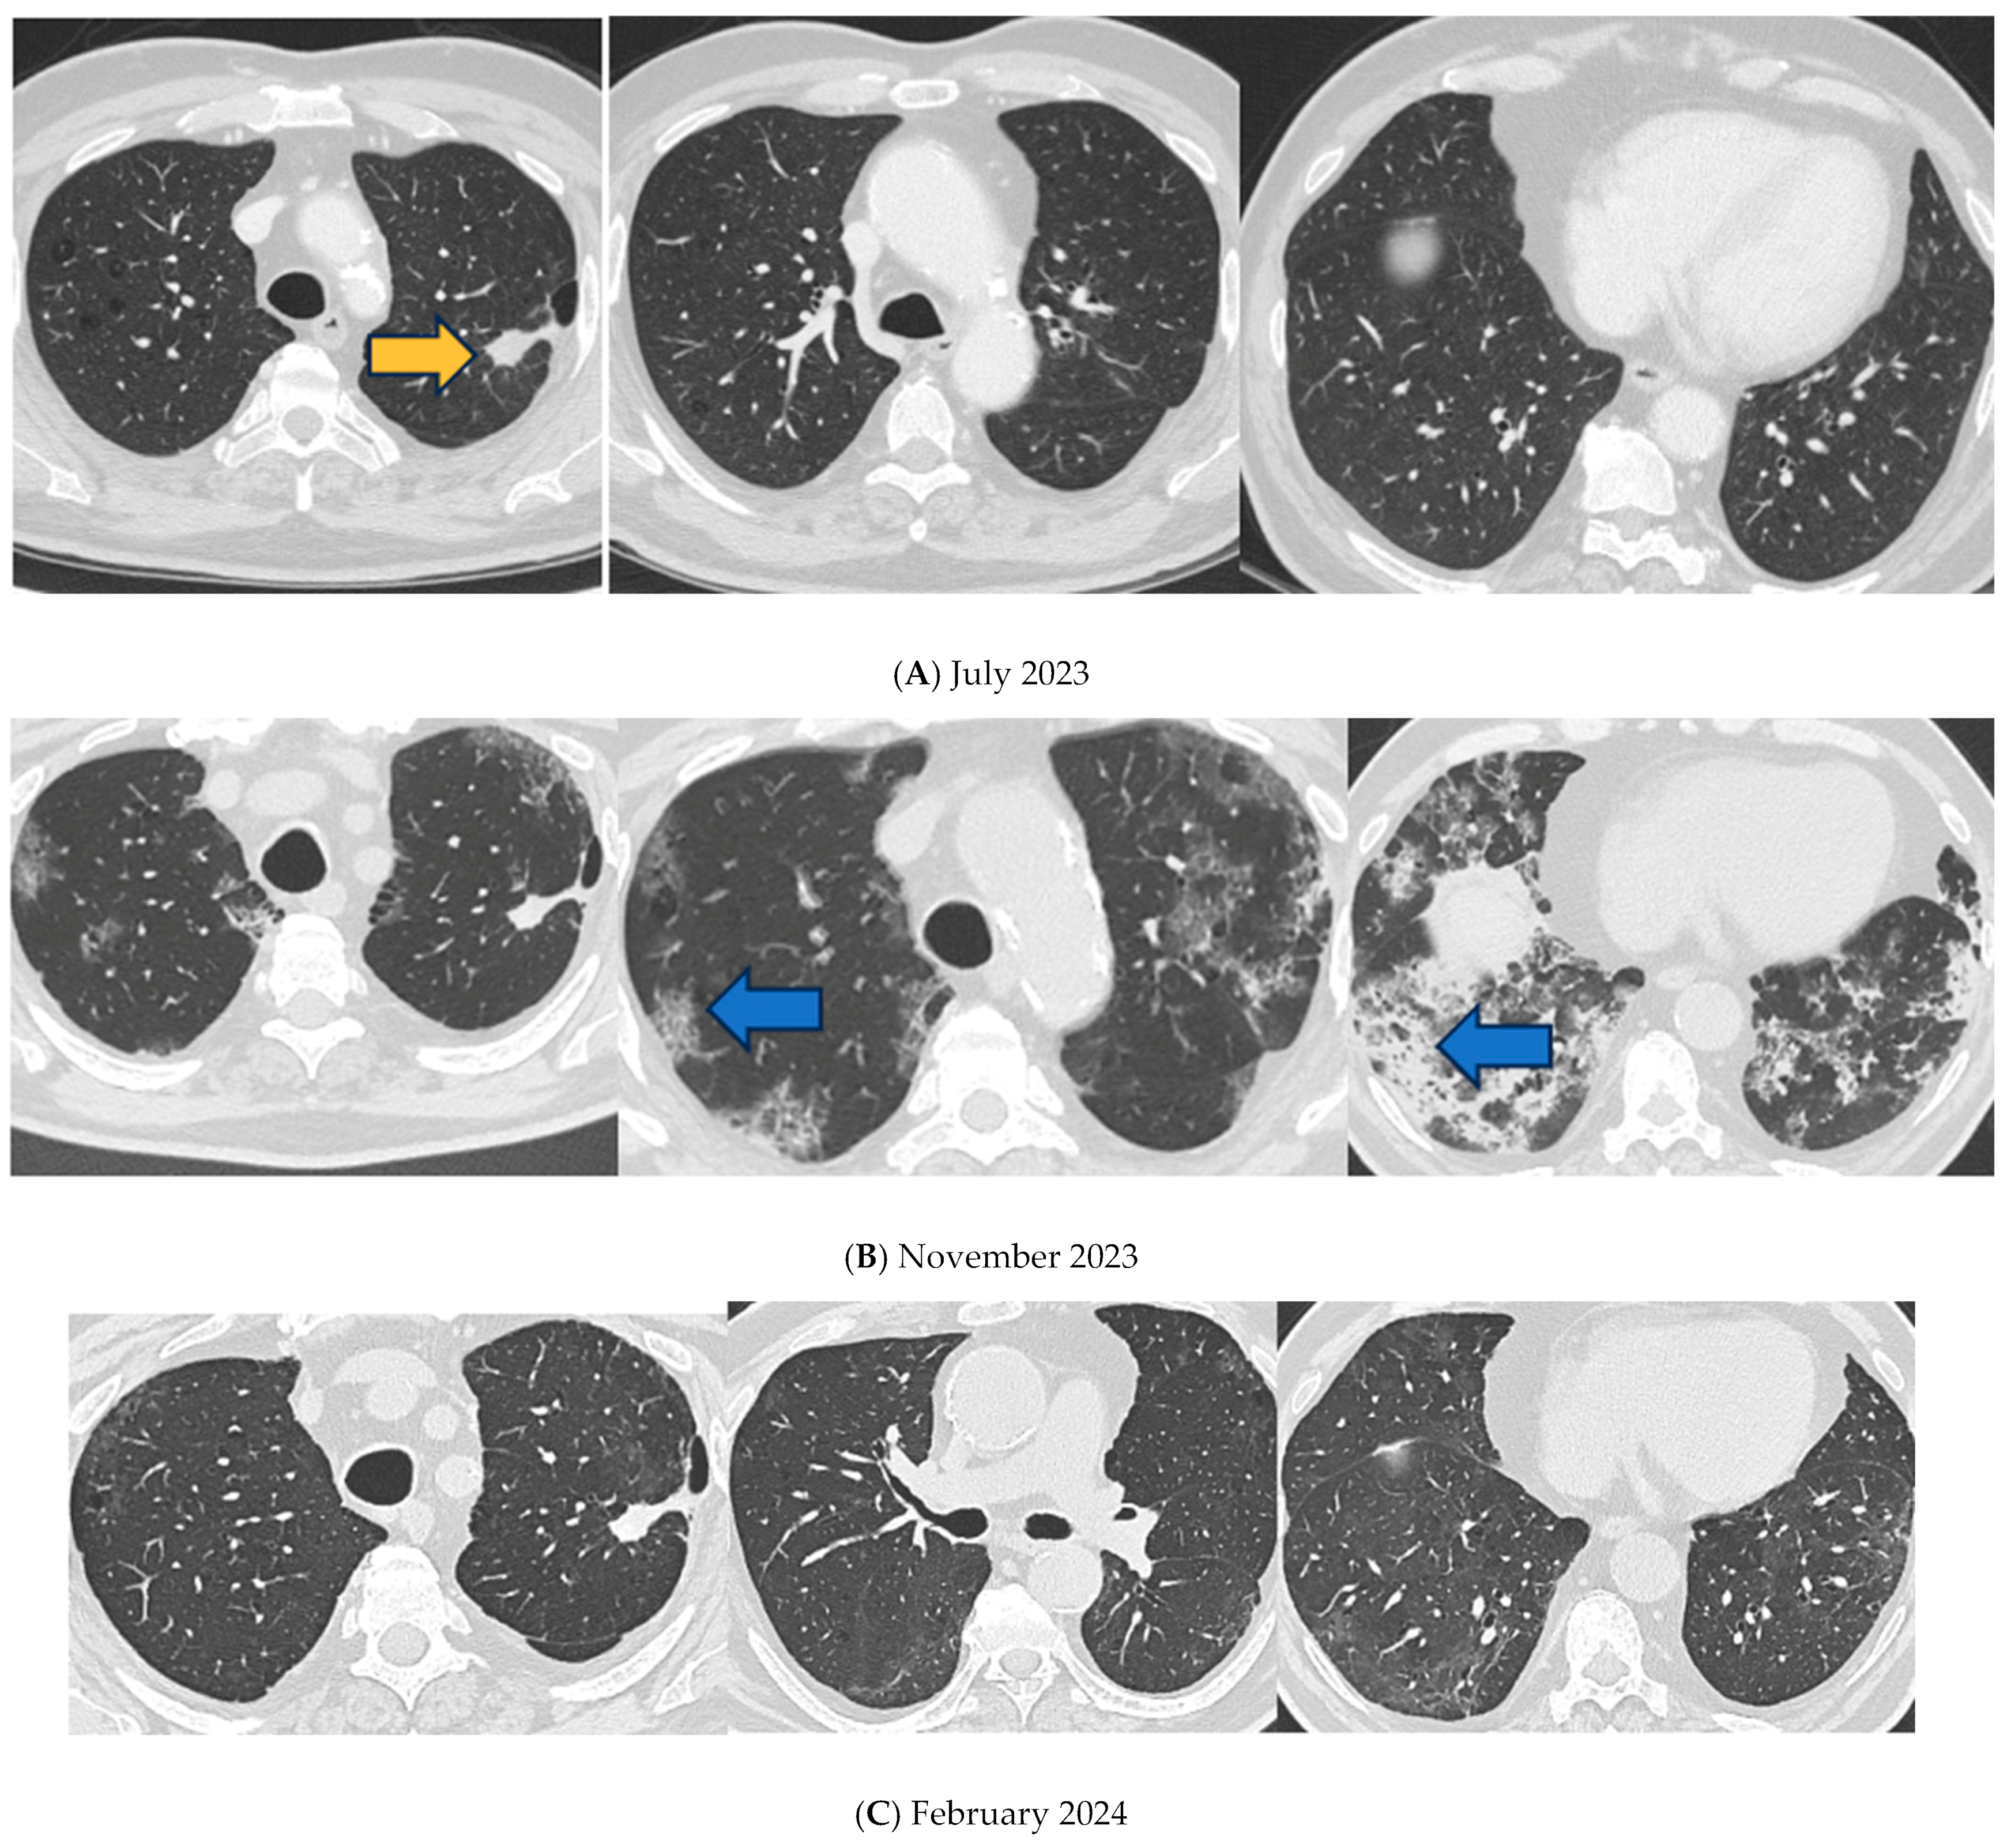

A Case of Pulmonary Fibrosis and COVID-19-Related Pneumonia in a Pembrolizumab-Treated Patient

2. Detailed Case Presentation